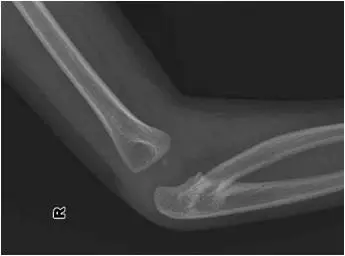

2 歲男孩因右上肢活動受限,被父母帶來求診,右肘部的 X光檢查結果如附圖,該男孩右上肢活動受限最嚴重的是下列何種動作?

本題考查兒童肘關節骨折脫位的影像學辨識與功能受限判斷。X 光顯示右肘部 Monteggia 骨折脫位(Monteggia fracture-dislocation),為兒童常見的肘部複合損傷,表現為近端尺骨骨折合併橈骨頭(radial head)脫位,直接影響前臂旋轉功能。

圖一(側位 X 光): 肘關節側位影像可見橈骨頭明顯向前移位,偏離正常與肱骨小頭(capitellum)的對位關係(radio-capitellar line 中斷)。近端尺骨可見骨折線,整體呈現前方橈骨頭脫位合併尺骨骨折的典型 Monteggia 第一型(Bado Type I)外觀。

圖二(前後位 X 光): 前後位影像清楚顯示橈骨頭自肱骨小頭之正常關節面脫出,移位至前外側。橈骨與尺骨的排列關係明顯異常,近端至中段尺骨可見骨折,進一步確認 Monteggia 骨折診斷。此影像為辨認橈骨頭脫位方向的關鍵視圖。